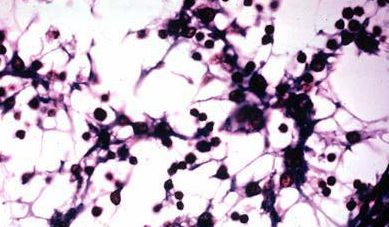

small-medium lymphocyte

reticular fibers and cells

loose and dense lymphoid tissue

Nodular

lymphoid tissue

Primary nodule

(unstimulated)

consist mostly of

B

lymphocytes